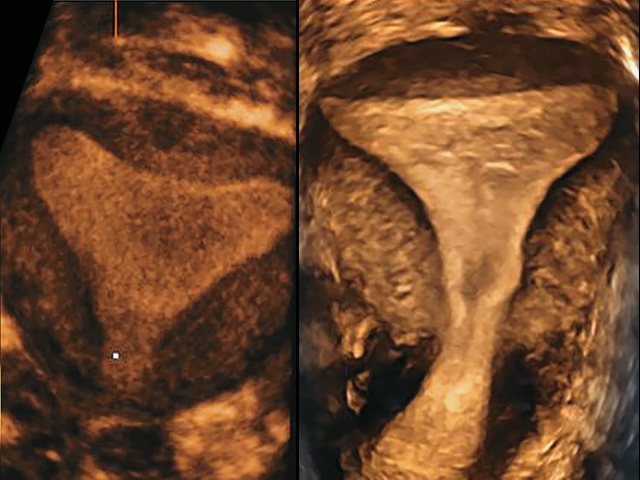

В настоящее исследование не были включены случаи, когда форма матки была отнесена визуально к нормальной/аркуатной (рис. 2), и случаи, когда по всем критериям форма матки была отнесена к перегородчатой (рис. 3).

В исследование вошло 22 пациентки, у которых визуальная оценка не позволяла однозначно отнести форму матки к аркуатной или перегородчатой (рис. 4).

Рис. 4. Формы полости матки, включенные в исследование.